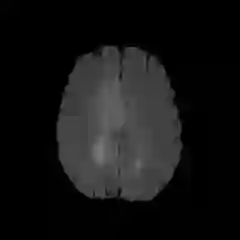

The Conditional Random Field as a Recurrent Neural Network layer is a recently proposed algorithm meant to be placed on top of an existing Fully-Convolutional Neural Network to improve the quality of semantic segmentation. In this paper, we test whether this algorithm, which was shown to improve semantic segmentation for 2D RGB images, is able to improve segmentation quality for 3D multi-modal medical images. We developed an implementation of the algorithm which works for any number of spatial dimensions, input/output image channels, and reference image channels. As far as we know this is the first publicly available implementation of this sort. We tested the algorithm with two distinct 3D medical imaging datasets, we concluded that the performance differences observed were not statistically significant. Finally, in the discussion section of the paper, we go into the reasons as to why this technique transfers poorly from natural images to medical images.

翻译:条件随机字段是一个经常性神经网络层,这是最近提出的一种算法,旨在置于现有的全进神经网络之上,以提高语义分离的质量。在本文中,我们测试这一算法是否能够改善3D多式医学图像的语义分离质量。我们开发了一个算法,该算法适用于任何空间维度、输入/输出图像频道和参考图像频道。据我们所知,这是首次可公开得到的这种类型的实施。我们用两套不同的3D医学成像数据集测试了算法,我们的结论是,观察到的性能差异在统计上没有多大意义。最后,在论文的讨论部分,我们探讨了为什么这种技术从自然图像向医学图像传播不力的原因。